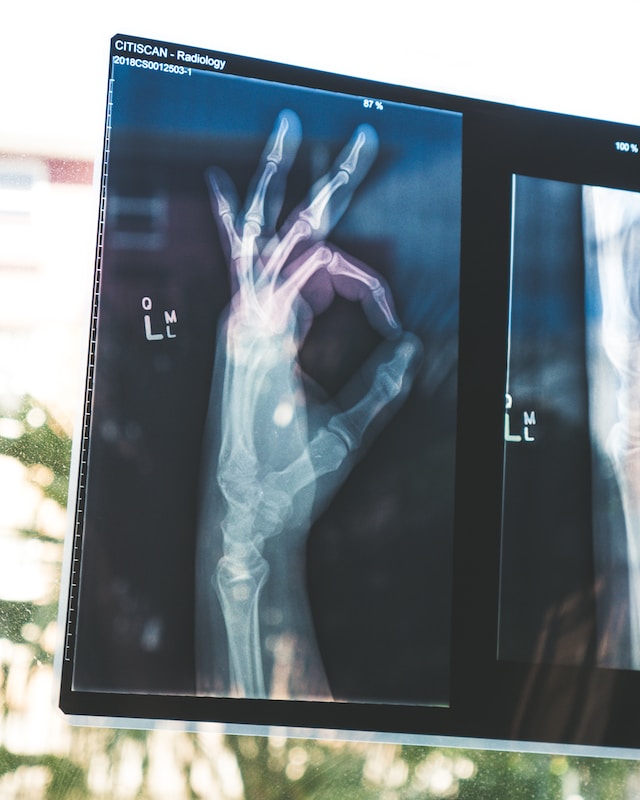

Introduction: Arm fractures can occur due to various reasons, ranging from accidents to sports injuries. Understanding the common causes of arm fractures is essential for taking preventive measures and ensuring safety. In this article, we will explore the primary causes of arm fractures and provide tips on how to stay safe and minimize the risk of such injuries.

Conclusion: Arm fractures can result from various causes, including falls, sports injuries, motor vehicle accidents, workplace accidents, and age-related factors. By understanding these common causes and taking preventive measures, individuals can significantly reduce the risk of arm fractures. Practicing safety precautions, using protective gear, following proper technique, and maintaining overall bone health are vital steps towards preventing arm fractures and ensuring personal well-being.